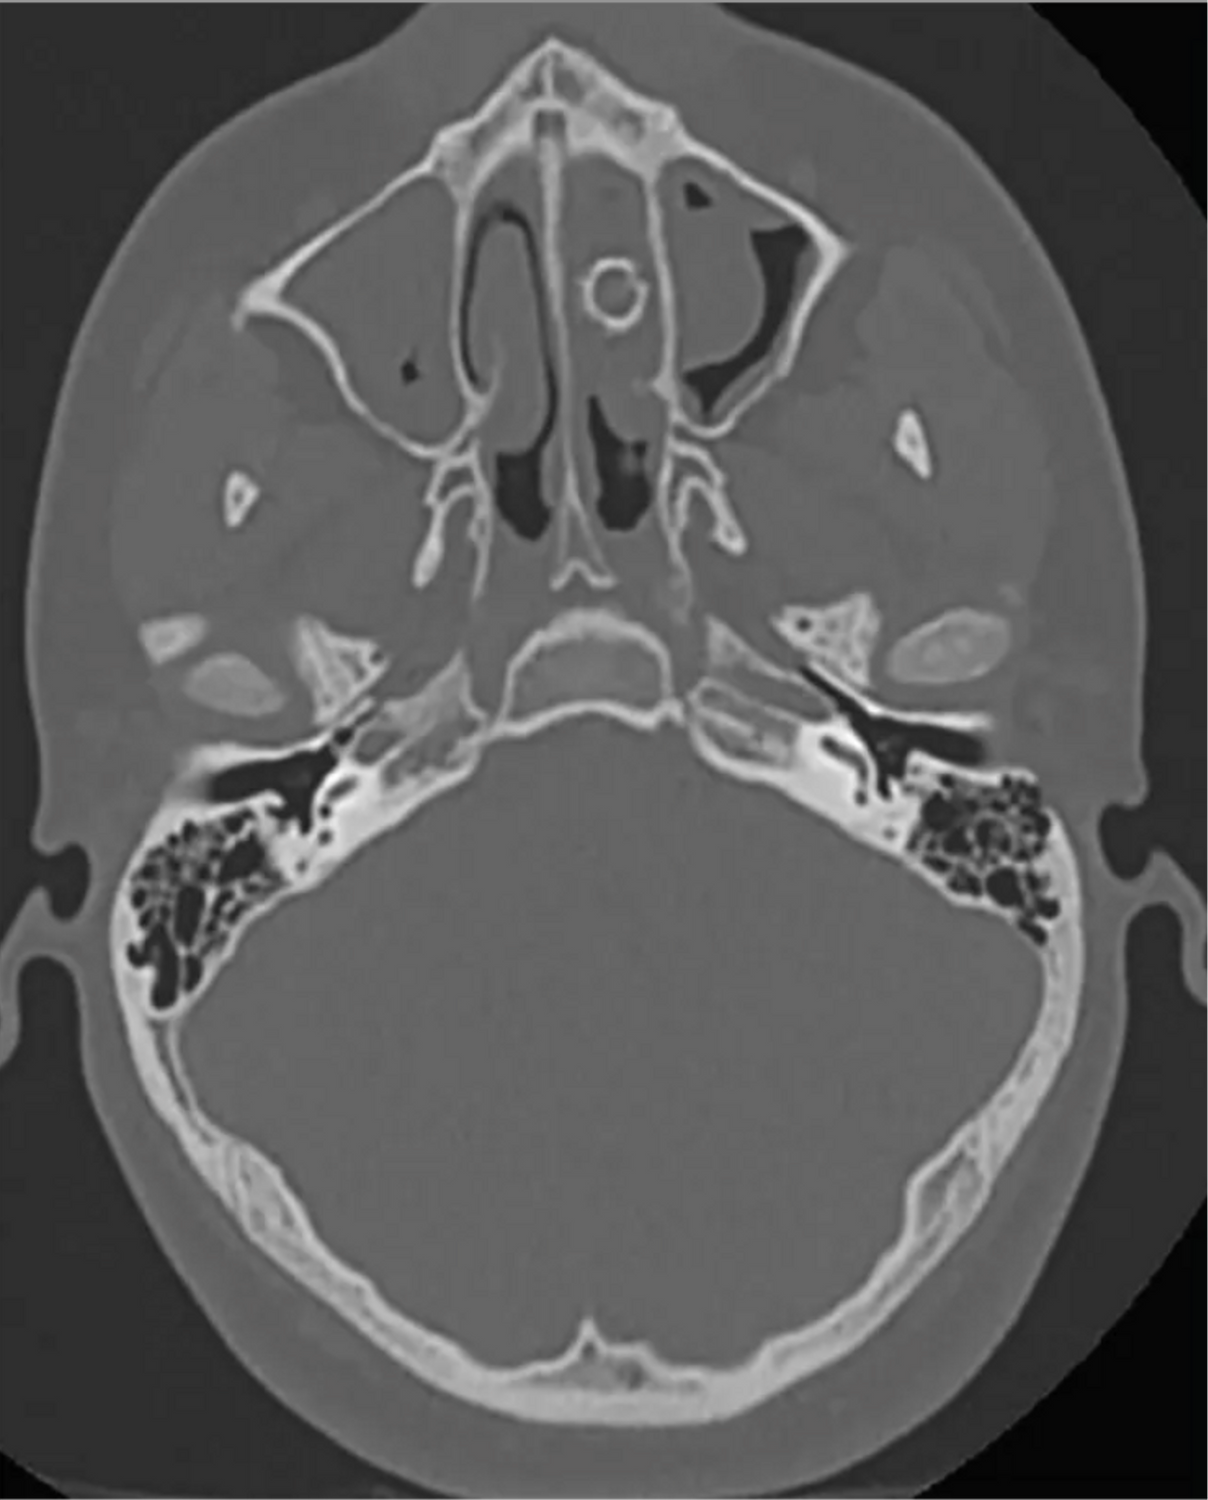

Ein bei einem weiteren Arzttermin angefertigter CT-Scan offenbarte, was die Ursache für die Probleme des zu dem Zeitpunkt 16-Jährigen herrührten.